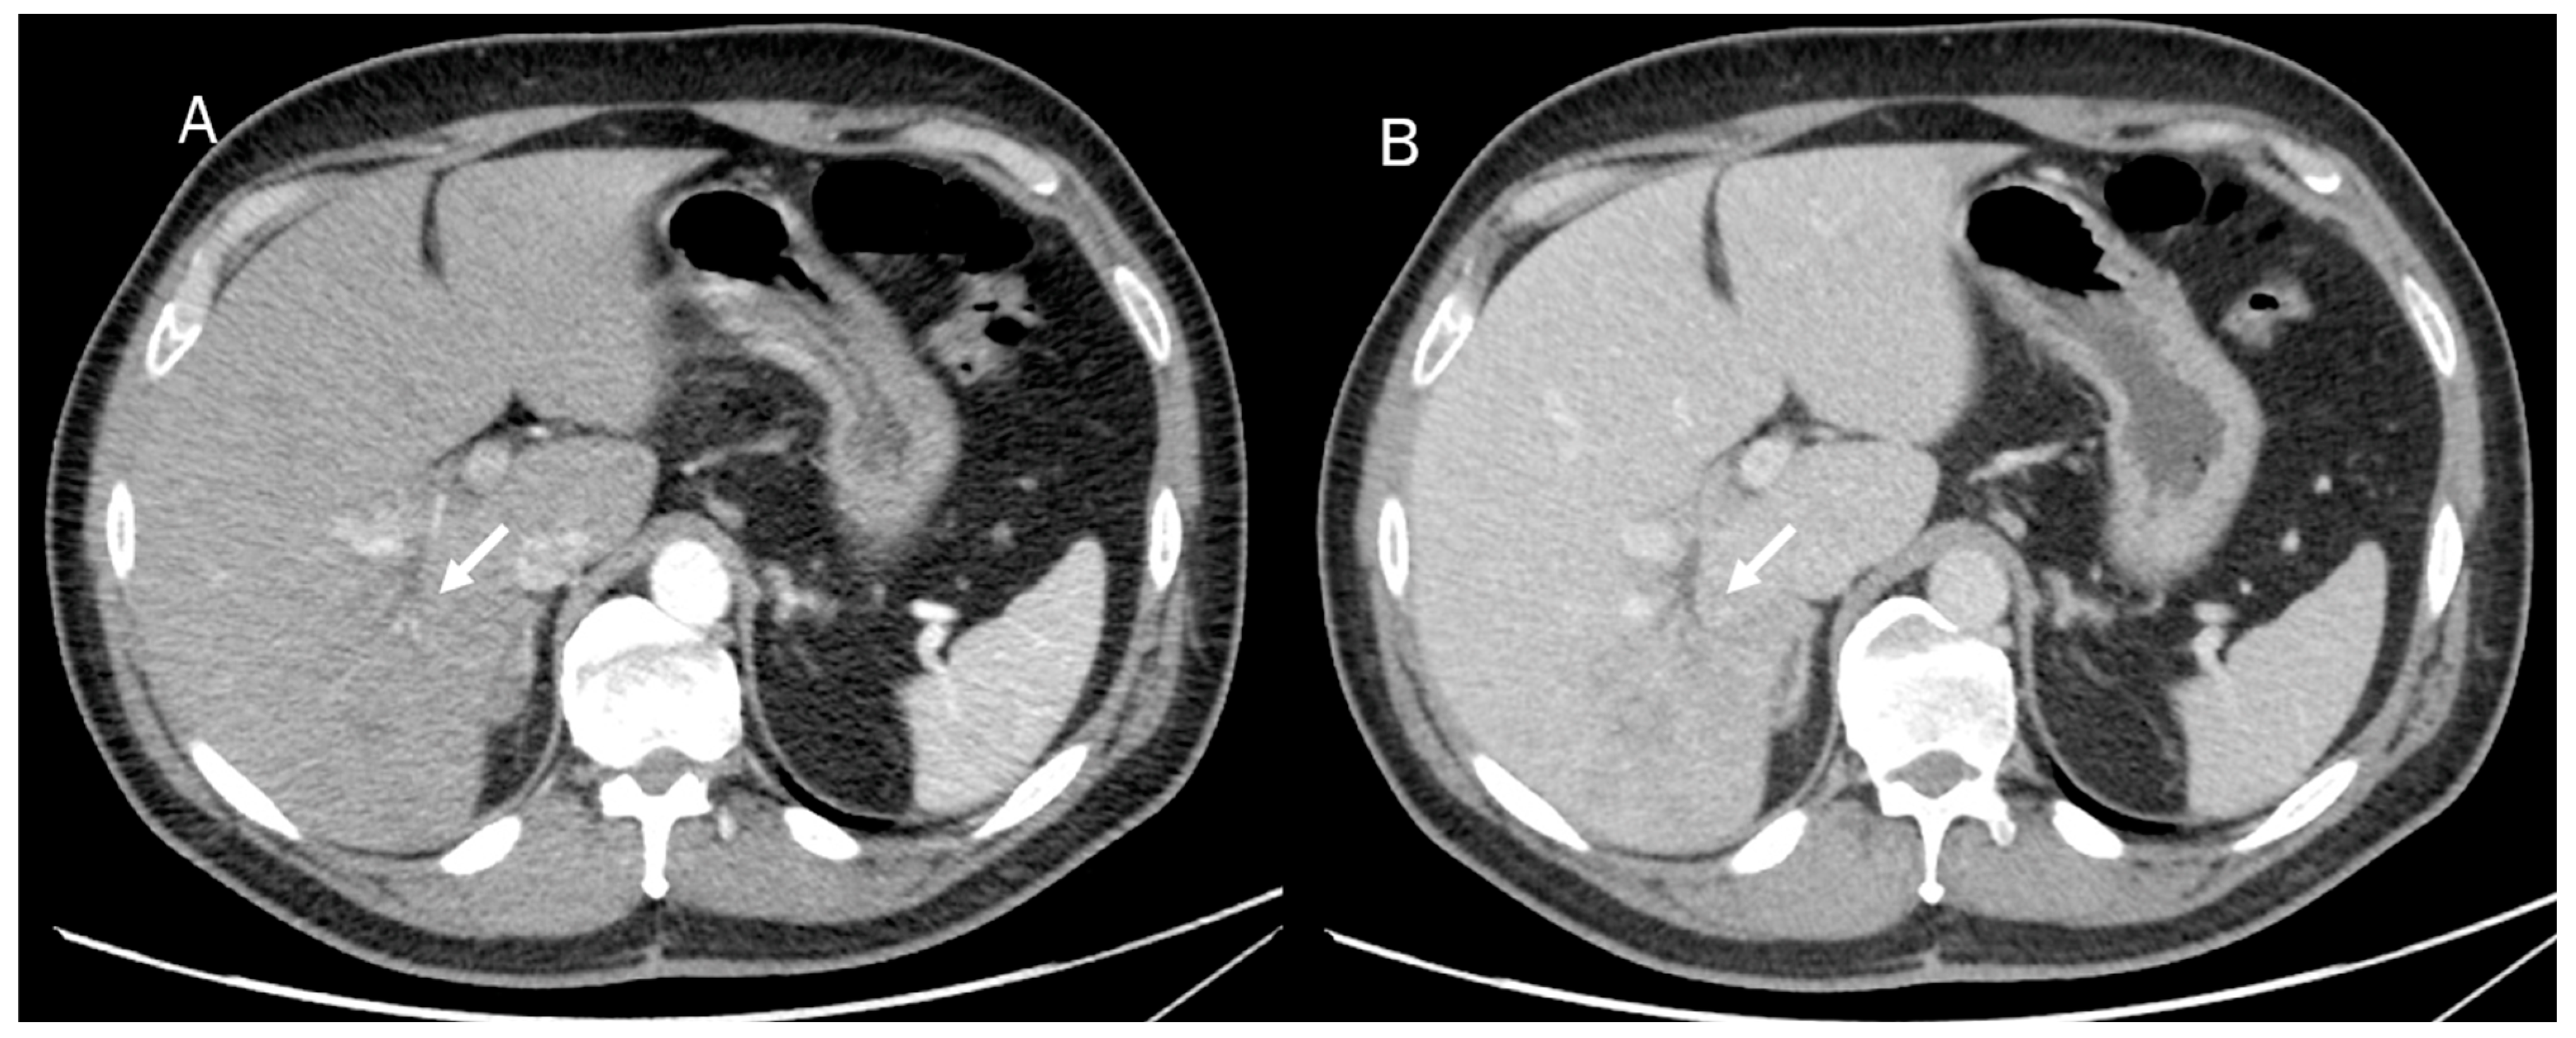

Mass-forming ICC usually appears at basal CT as a hypodense lesion presenting either a well-defined border or an infiltrative pattern without its own capsule (Figure 4). It is associated with heokpatic capsule retraction in about 20% of cases [108,109]. After contrast administration, the nodule shows initial peripheral rim enhancement, followed by progressive and concentric filling with contrast material as an effect of fibrosis, which is slow to enhance but retains the intravenous contrast agent [110,111].

Figure 4.

CT assessment of ICC (arrow) during arterial (A) and portal (B) phase of contrast study. The lesion (arrow) shows an infiltrative pattern with biliary tree dilatation.